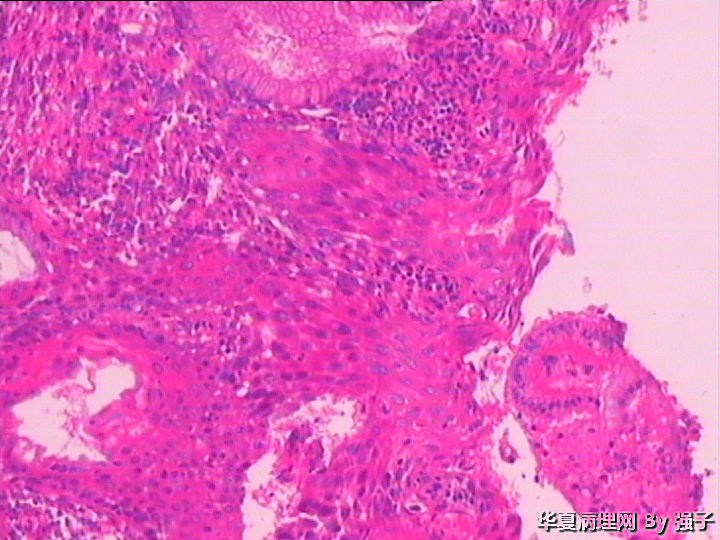

紧急求助,化生?还是累腺?

女,29岁

属于CIN病变吧,有累及腺体的地方,患者还满年轻!

高级别上皮内瘤变,累腺

高级别上皮内瘤变,累腺,第4图有核分裂

CINII-III累腺,学习中

CIN2级累腺